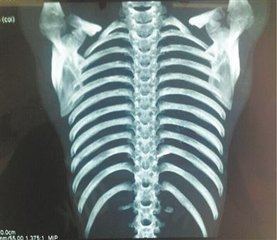

顾客CT照片